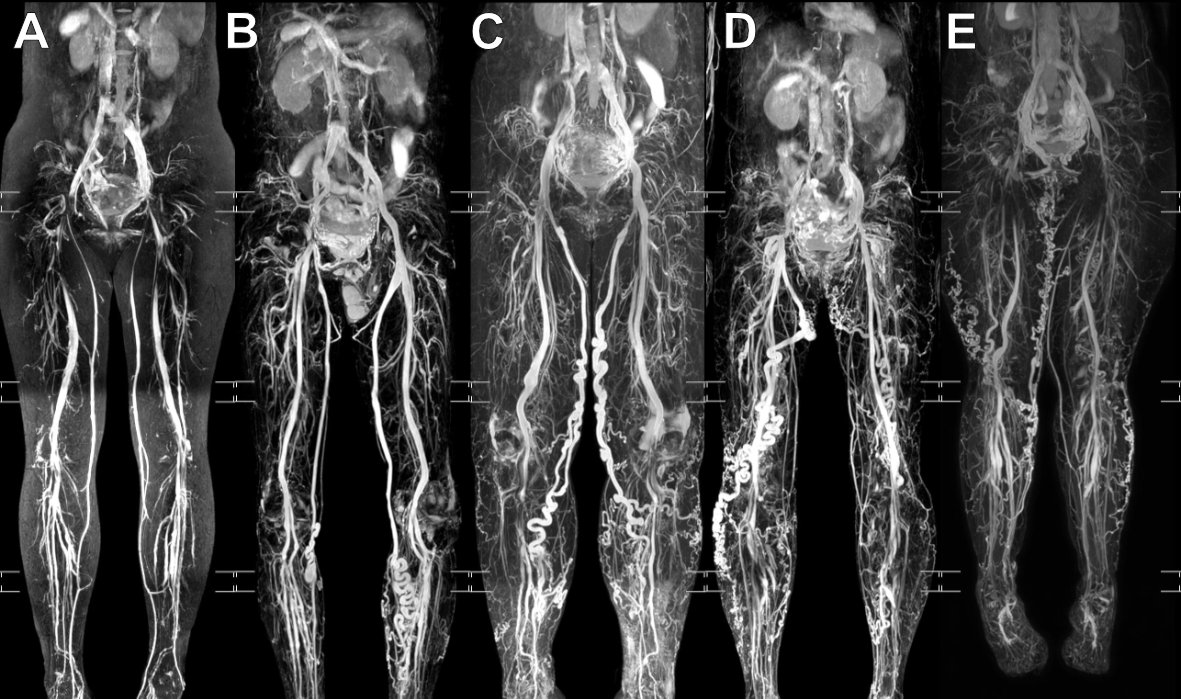

比較輕微的是只有大隱靜脈的遠端(小腿內側)靜脈變型(圖B),久而久之連大腿的大隱靜脈點變型了(圖C)。

這些病人的靜脈曲張就不是像之前提到的擴大、扭曲、變型,而是像血絲或是泡麵一樣,細細一把的纏繞散布(圖D、E)。

明顯的骨盆充合併骨盆腔滲漏及雙足靜脈曲張。

我們可以從正面同時看到兩條腿有的骨盆腔滲漏,需要單腿模式才可以看清楚滲漏的正確走向。(B.C.)